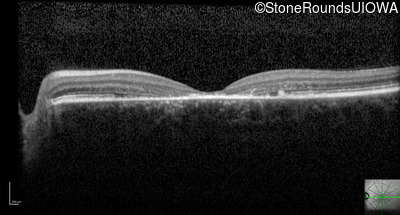

Optical Coherence Tomography - Left - 20/150

Exemplar / OCT Stack

Optical Coherence Tomography - Left - 20/160 +1